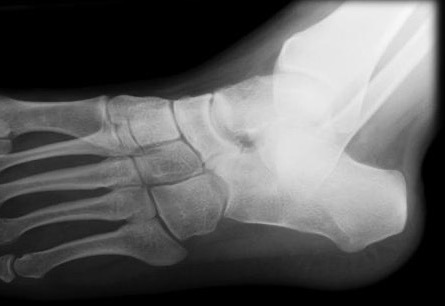

Xray

| Talar beaking | C Sign | Harris axial view | Ball and socket ankle joint |

|---|---|---|---|

| Traction spur due to increased stress | Medial outline talar dome and posterior sustenaculum tali |

40 degree axial view Ski jump view Visualize middle facet |

Secondary to rigid subtalar joint Develops to allow inversion / eversion |

Talar beaking with C sign